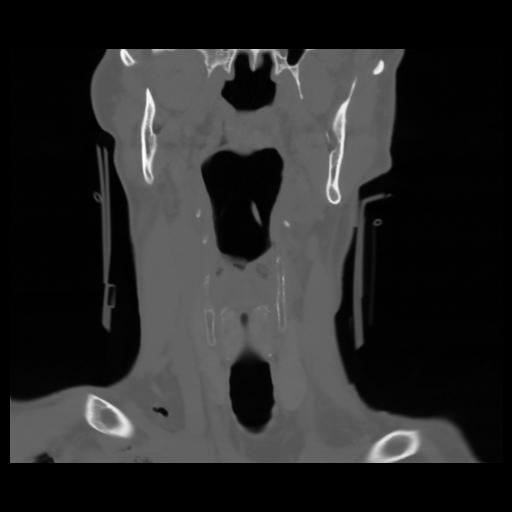

13 P.BLANDAS,,Coronal,2.000,P.BLANDAS,Coronal,